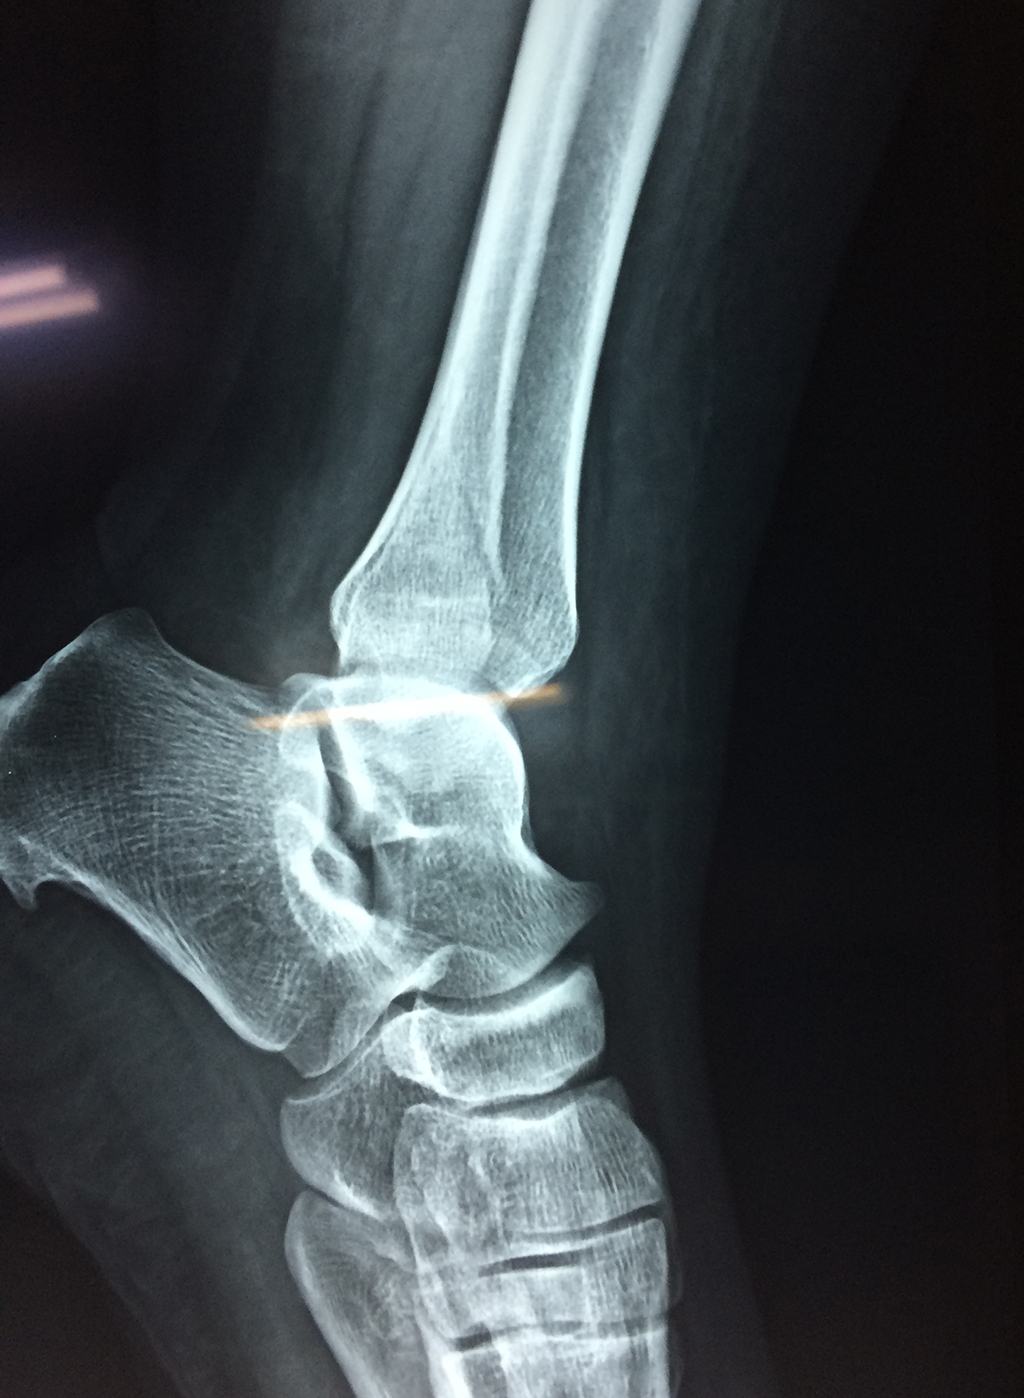

Una fractura de tobillo es la rotura de uno o más de los huesos del tobillo. Estas fracturas pueden ser:

Algunas fracturas de tobillo pueden requerir cirugía si:

• Los extremos de los huesos están desalineados entre sí (desplazados).

• La fractura se extiende hasta la articulación del tobillo (fractura intra-articular).